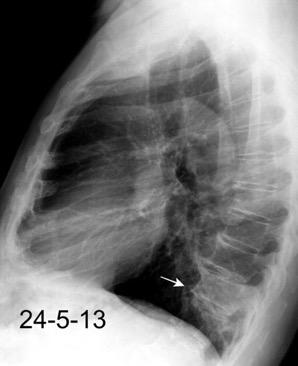

100. TUMOR FANTASMA

102. TUMOR FANTASMA. HEMATOCELE

En relación con trasudados tabicados. Insuficiencia cardiaca

Hipoalbuminemia

Cirrosis / Fallo renal.

Operado aneurisma (prótesis). Líquido tabicado en cisuras

Derrame pleural “encapsulado”

“Tumor fantasma”

Asociado a fallo cardiaco. ( “Pleuritis adhesiva”). Buch KP. Chest. 2000